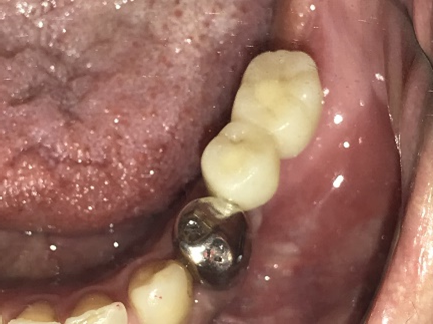

ブリッジの支台になっている奥の歯が、被せ物の中で虫歯になり、支台の役割を果たさず、前方の歯のみで支えられていました。前方の歯をそのままにして、後方の部分を切り離すと、そのまま取れてきました。中は、虫歯で歯根しか残っていない状況でした。この歯は、根管治療後、単独でオールセラミック冠を被せ、歯のないところにインプラントを埋入しました。

冠の中で大きな虫歯になり支台の役割を果たしていませんでした。

【インプラント埋入前】

冠はブリッジを切断しただけで取れてきました。軟化象牙質を取り除いたところ、歯根しか残っていない状況で保存できるかどうかのぎりぎりのところでした。

After